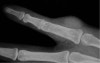

X-ray : Giant cell tumor of tendon sheath